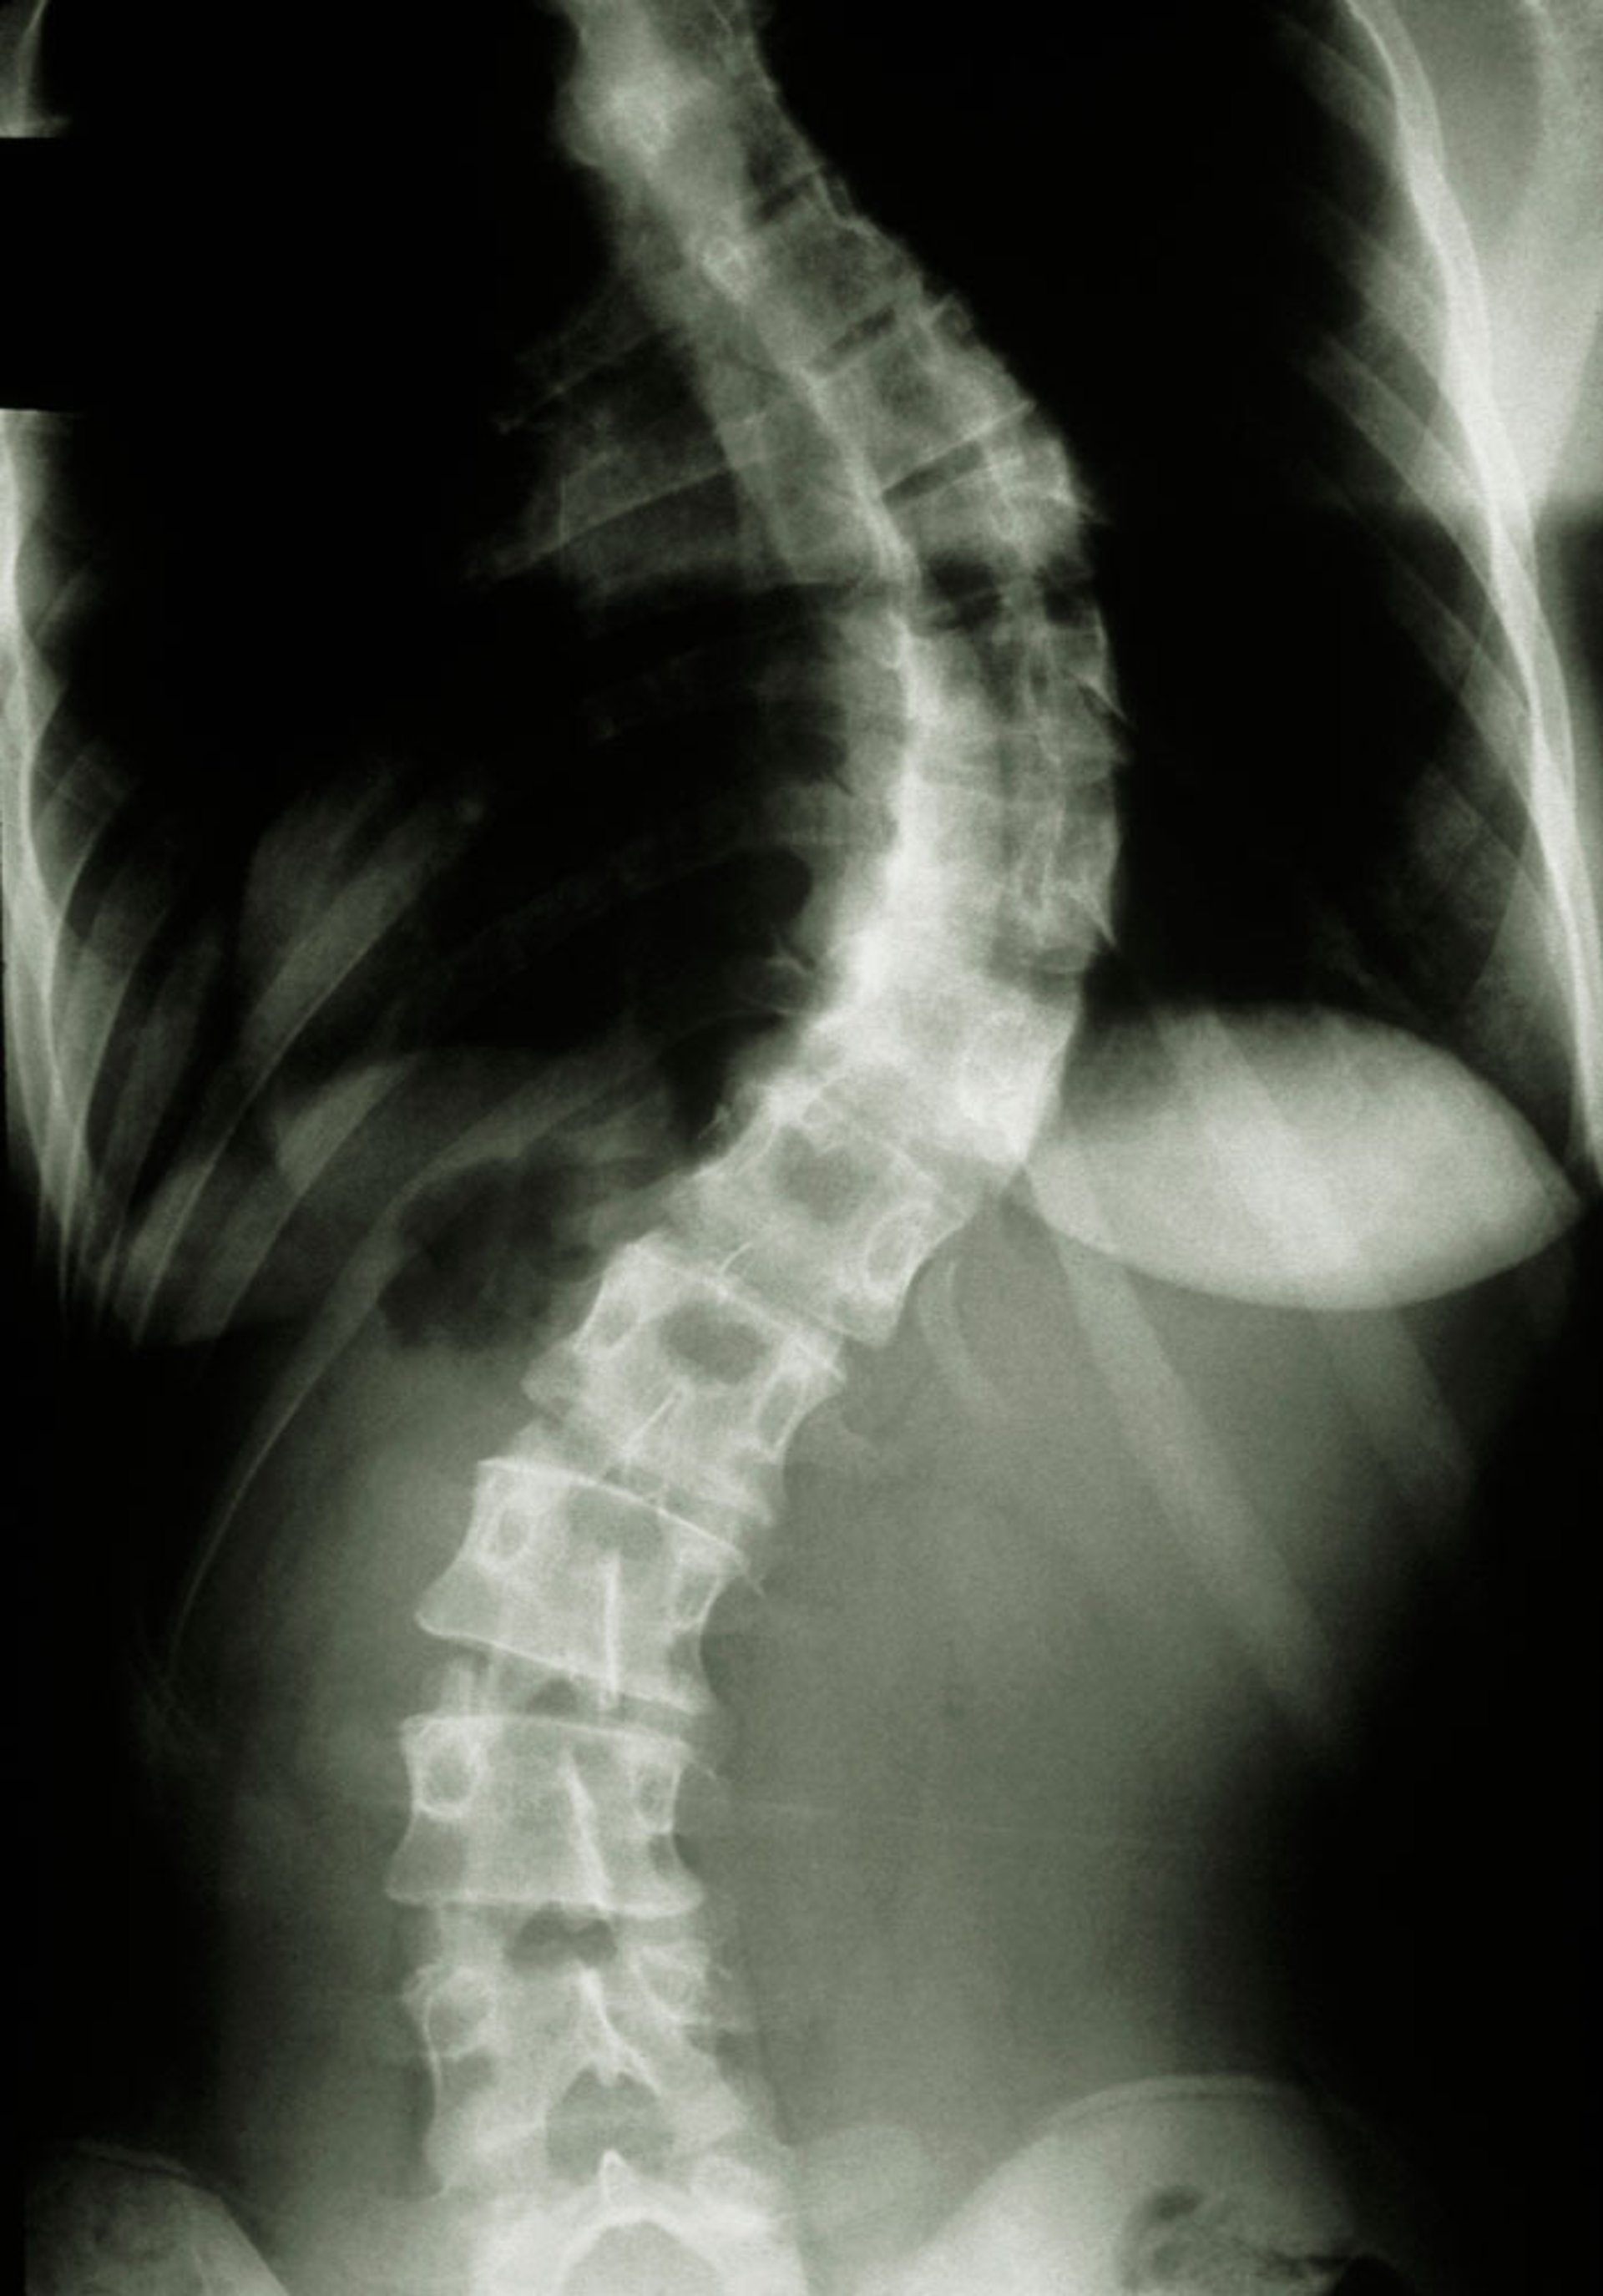

Cette photo montre une adolescente atteinte d'une scoliose sévère (courbure de la colonne vertébrale).

MEDICAL PHOTO NHS LOTHIAN/SCIENCE PHOTO LIBRARY